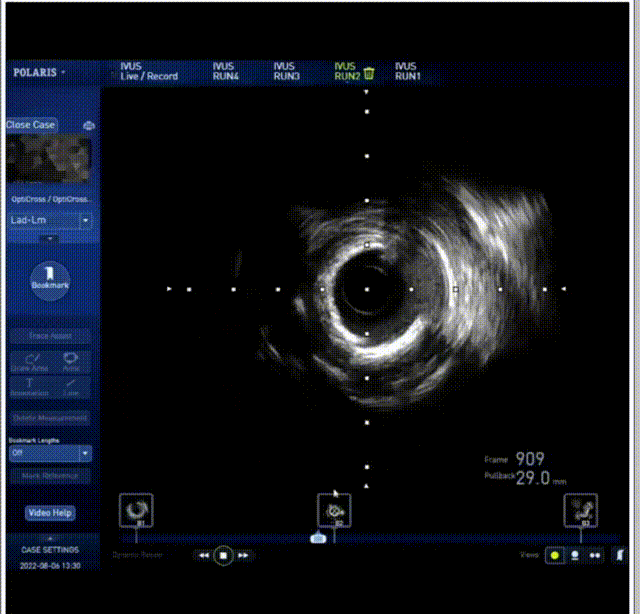

当日直播手术中行IVUS检查,提示患者前降支全程弥漫性钙化伴狭窄,近中段最重85%-90%狭窄、360度钙化、严重钙化病变长度32mm。由于钙化长度长、钙化非常严重、患者高龄、病变局部有扭曲、且钙化环管腔残余直径达2mm,都增加了手术的难度和风险,传统的钙化处理工具已经无法解决,所以高静主任选择用最新的冲击波球囊处理钙化病变。

术前IVUS 下可见360度钙化环

手术过程中,经2.0mm*15mm 球囊预扩前降支近、中段病变后,使用谱创医疗Sonico-CX 2.5mm*12mm 冲击波球囊置入前降支病变处,先后触发60次冲击波(6个周期,每个周期分别以4 atm 激发冲击波,再以8 atm 扩张成形)实施钙化斑块碎裂术,DSA下可见随着冲击波释放,球囊形状慢慢扩张。谱创医疗Sonico-CX冲击波球囊处理后复查IVUS,显示原钙化环断裂。经过充分的冲击波球囊预处理后,因钙化环得到松解,为进一步扩大管腔面积,用2.5mm *15mm高压球囊进一步扩开前降支近、中段病变,最后顺利放入药物洗脱支架。复查IVUS显示支架膨胀完全、贴壁良好,支架两端未见夹层及血肿,残余狭窄0%,复查造影显示远端血流通畅。

钙化环被冲击波打断